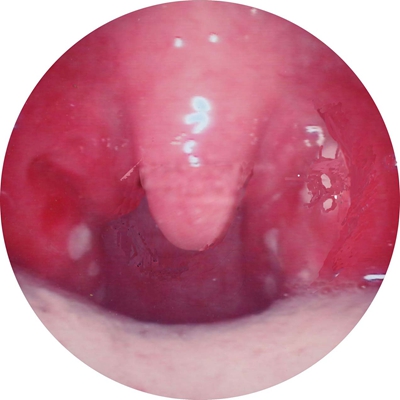

扁桃體惡性腫瘤圖片

扁桃體癌圖 (69)